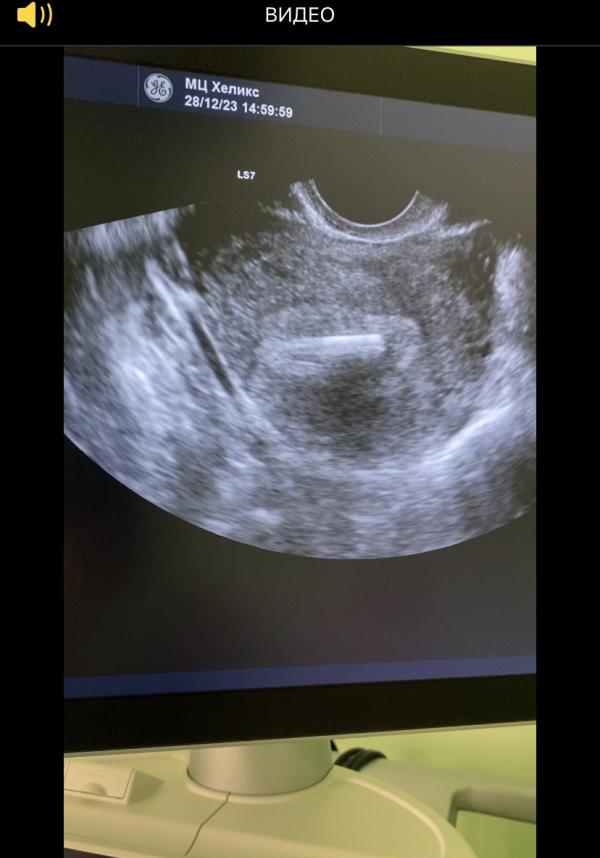

При проведении УЗИ : яичники без патологии ,желтое тело в правом яичнике, в полости матки определяется поперечно расположенная спираль, которая проникала в стенку матки ( справа) . Но это ещё не всё 🙂

По заднему листу эндометрия определяется плодное яйцо небольшого размера ( 4мм на втором фото)